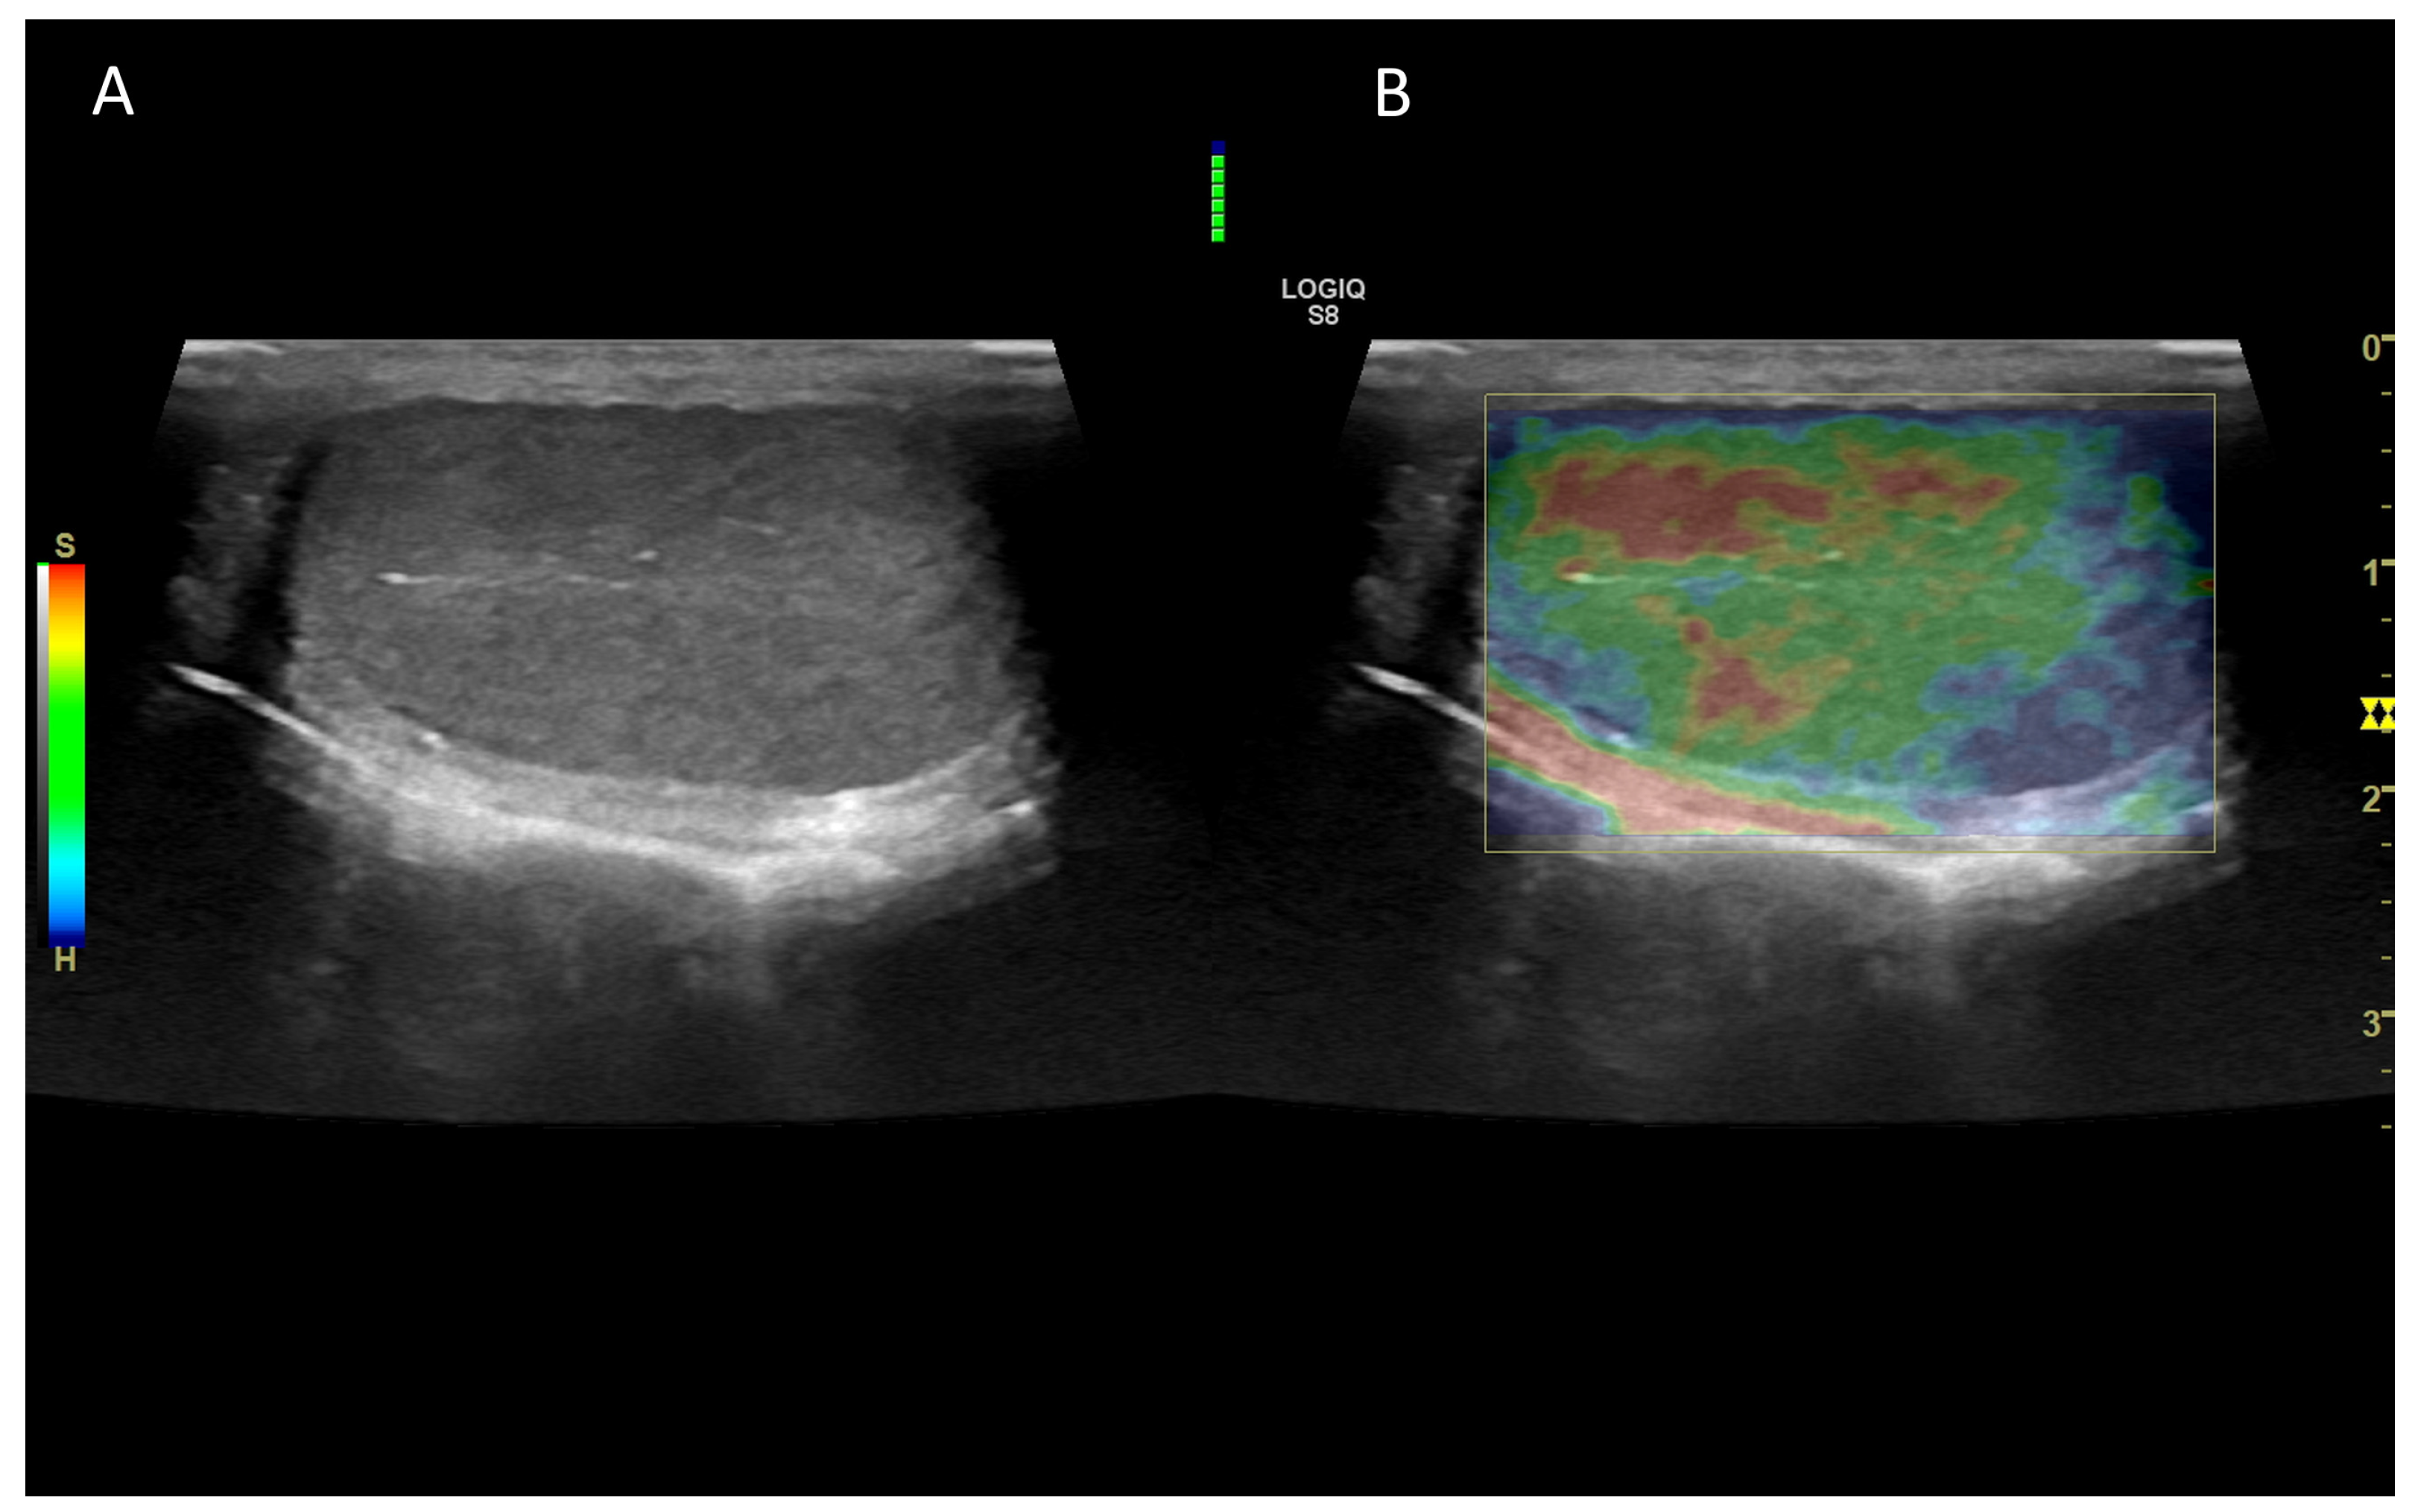

7. Ultrasound Elastography

7.1. Technology and Applications

7.2. Normal Findings

7.3. Abnormal Findings

- Holdsworth, A.; Bradley, K.; Birch, S.; Browne, W.J.; Barberet, V. Elastography of the Normal Canine Liver, Spleen and Kidneys: Canine Elastography. Vet. Radiol. Ultrasound 2014, 55, 620–627. [Google Scholar] [CrossRef]

- Jeon, S.; Lee, G.; Lee, S.-K.; Kim, H.; Yu, D.; Choi, J. Ultrasonographic Elastography of the Liver, Spleen, Kidneys, and Prostate in Clinically Normal Beagle Dogs: Ultrasonographic Elastography in Normal Dogs. Vet. Radiol. Ultrasound 2015, 56, 425–431. [Google Scholar] [CrossRef]

- Feliciano, M.A.R.; Maronezi, M.C.; Simões, A.P.R.; Uscategui, R.R.; Maciel, G.S.; Carvalho, C.F.; Canola, J.C.; Vicente, W.R.R. Acoustic Radiation Force Impulse Elastography of Prostate and Testes of Healthy Dogs: Preliminary Results. J. Small Anim. Pr. 2015, 56, 320–324. [Google Scholar] [CrossRef] [PubMed]

- Feliciano, M.A.R.; Maronezi, M.C.; Simões, A.P.R.; Maciel, G.S.; Pavan, L.; Gasser, B.; Silva, P.; Uscategui, R.R.; Carvalho, C.F.; Canola, J.C.; et al. Acoustic Radiation Force Impulse (ARFI) Elastography of Testicular Disorders in Dogs: Preliminary Results. Arq. Bras. Med. Vet. Zootec. 2016, 68, 283–291. [Google Scholar] [CrossRef]

- Glińska-Suchocka, K.; Jankowski, M.; Kubiak, K.; Spużak, J.; Dzimira, S. Sonoelastography in Differentiation of Benign and Malignant Testicular Lesion in Dogs. Pol. J. Vet. Sci. 2014, 17, 487–491. [Google Scholar] [CrossRef]